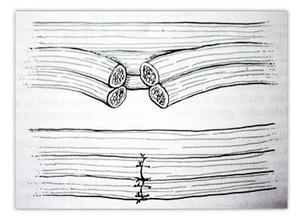

常见的周围神经损伤症状主要有哪些?对于周围神经损伤的治疗,认识其主要症状很有必要。只有了解了其主…「 阅读全文 」